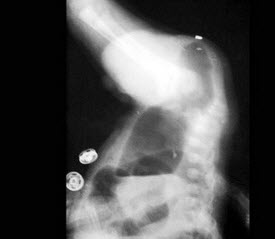

10、单项选择题

男,78岁,进行性吞咽困难1月余,结合图像,最可能的诊断为()